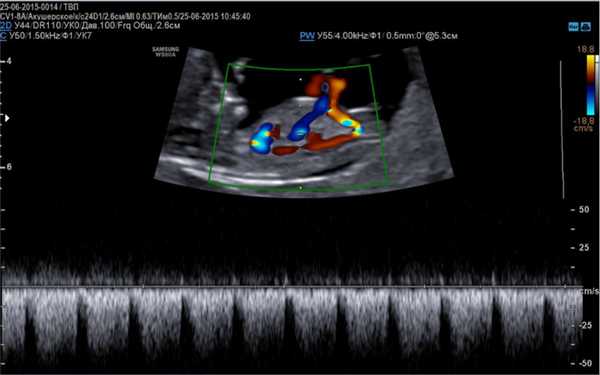

Для выявления тахикардии, врачи проводят допплеровское исследование, так как это лучший метод для анализа состояния эмбриона. Исследование позволяет оценить сокращение предсердий и желудочков и выявить движения крови в сердце. Обязательной является дифференциальная диагностика, которая основана на нескольких видах тахиаритмии, возникающих у плода.

Основой для качественной диагностики является наличие программы, позволяющей определить функциональное состояние сердечно-сосудистой системы на приборе, оснащенным специальным датчиком, имеющим частоту сканирования не менее 5 МГц, а также цветное картирование системы кровообращения и доплер.

- Доплер эхокардиография, более расширенная методика, определяющая гемодинамику, ритмичность и сократительную способность сердца, направленность тока крови по сосудам.